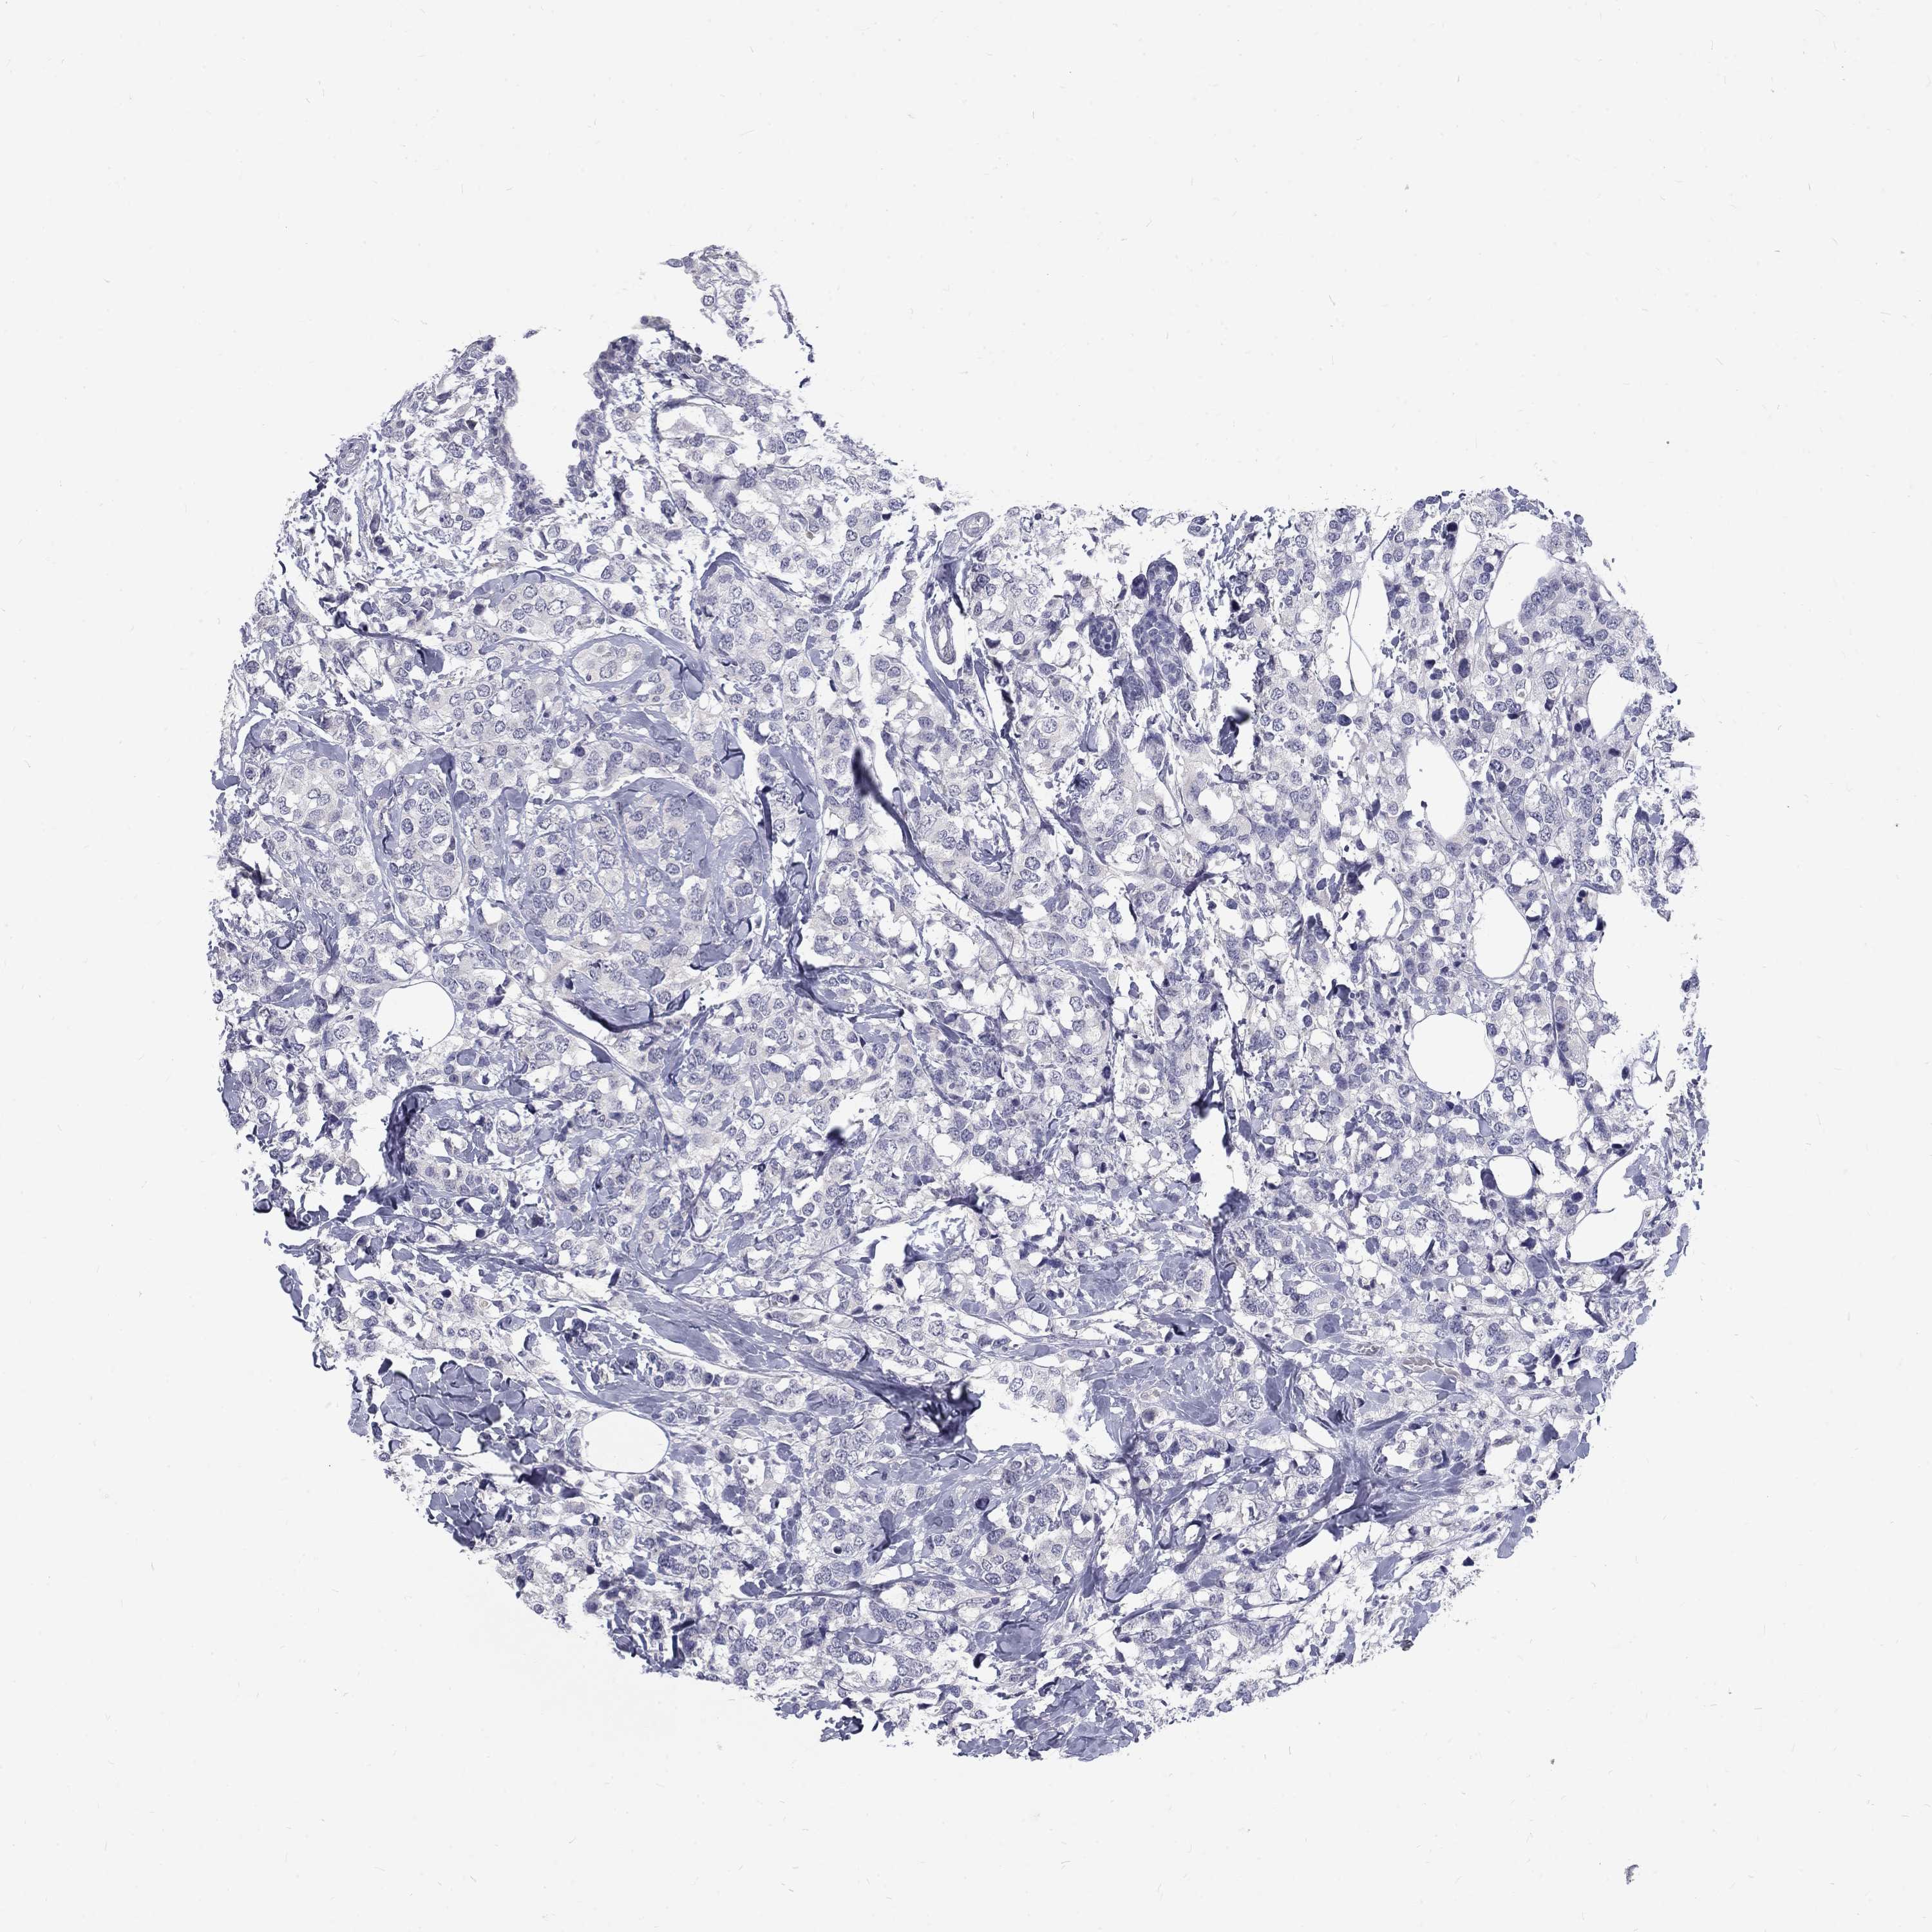

Breast cancer

Human cancer

Breast invasive carcinoma